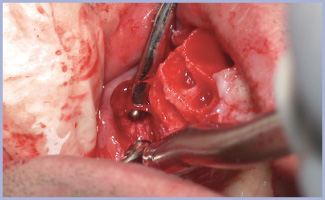

La seconda fase chirurgica è stata effettuata con piccole incisioni semilunari in modo da aumentare la banda di gengiva aderente vestibolare e migliorare il profilo di emergenza protesico (figg. 8-9).

- Fig. 8 – Seconda fase chirurgica a 6 mesi di distanza

- Fig. 9 – Incisioni semilunari per aumentare la banda di gengiva aderente vestibolare e migliorare il profilo d’emergenza protesico